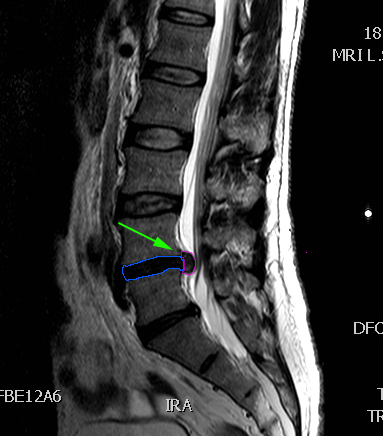

Κήλη οσφυϊκού μεσοσπονδυλίου δίσκου, επίπεδο |